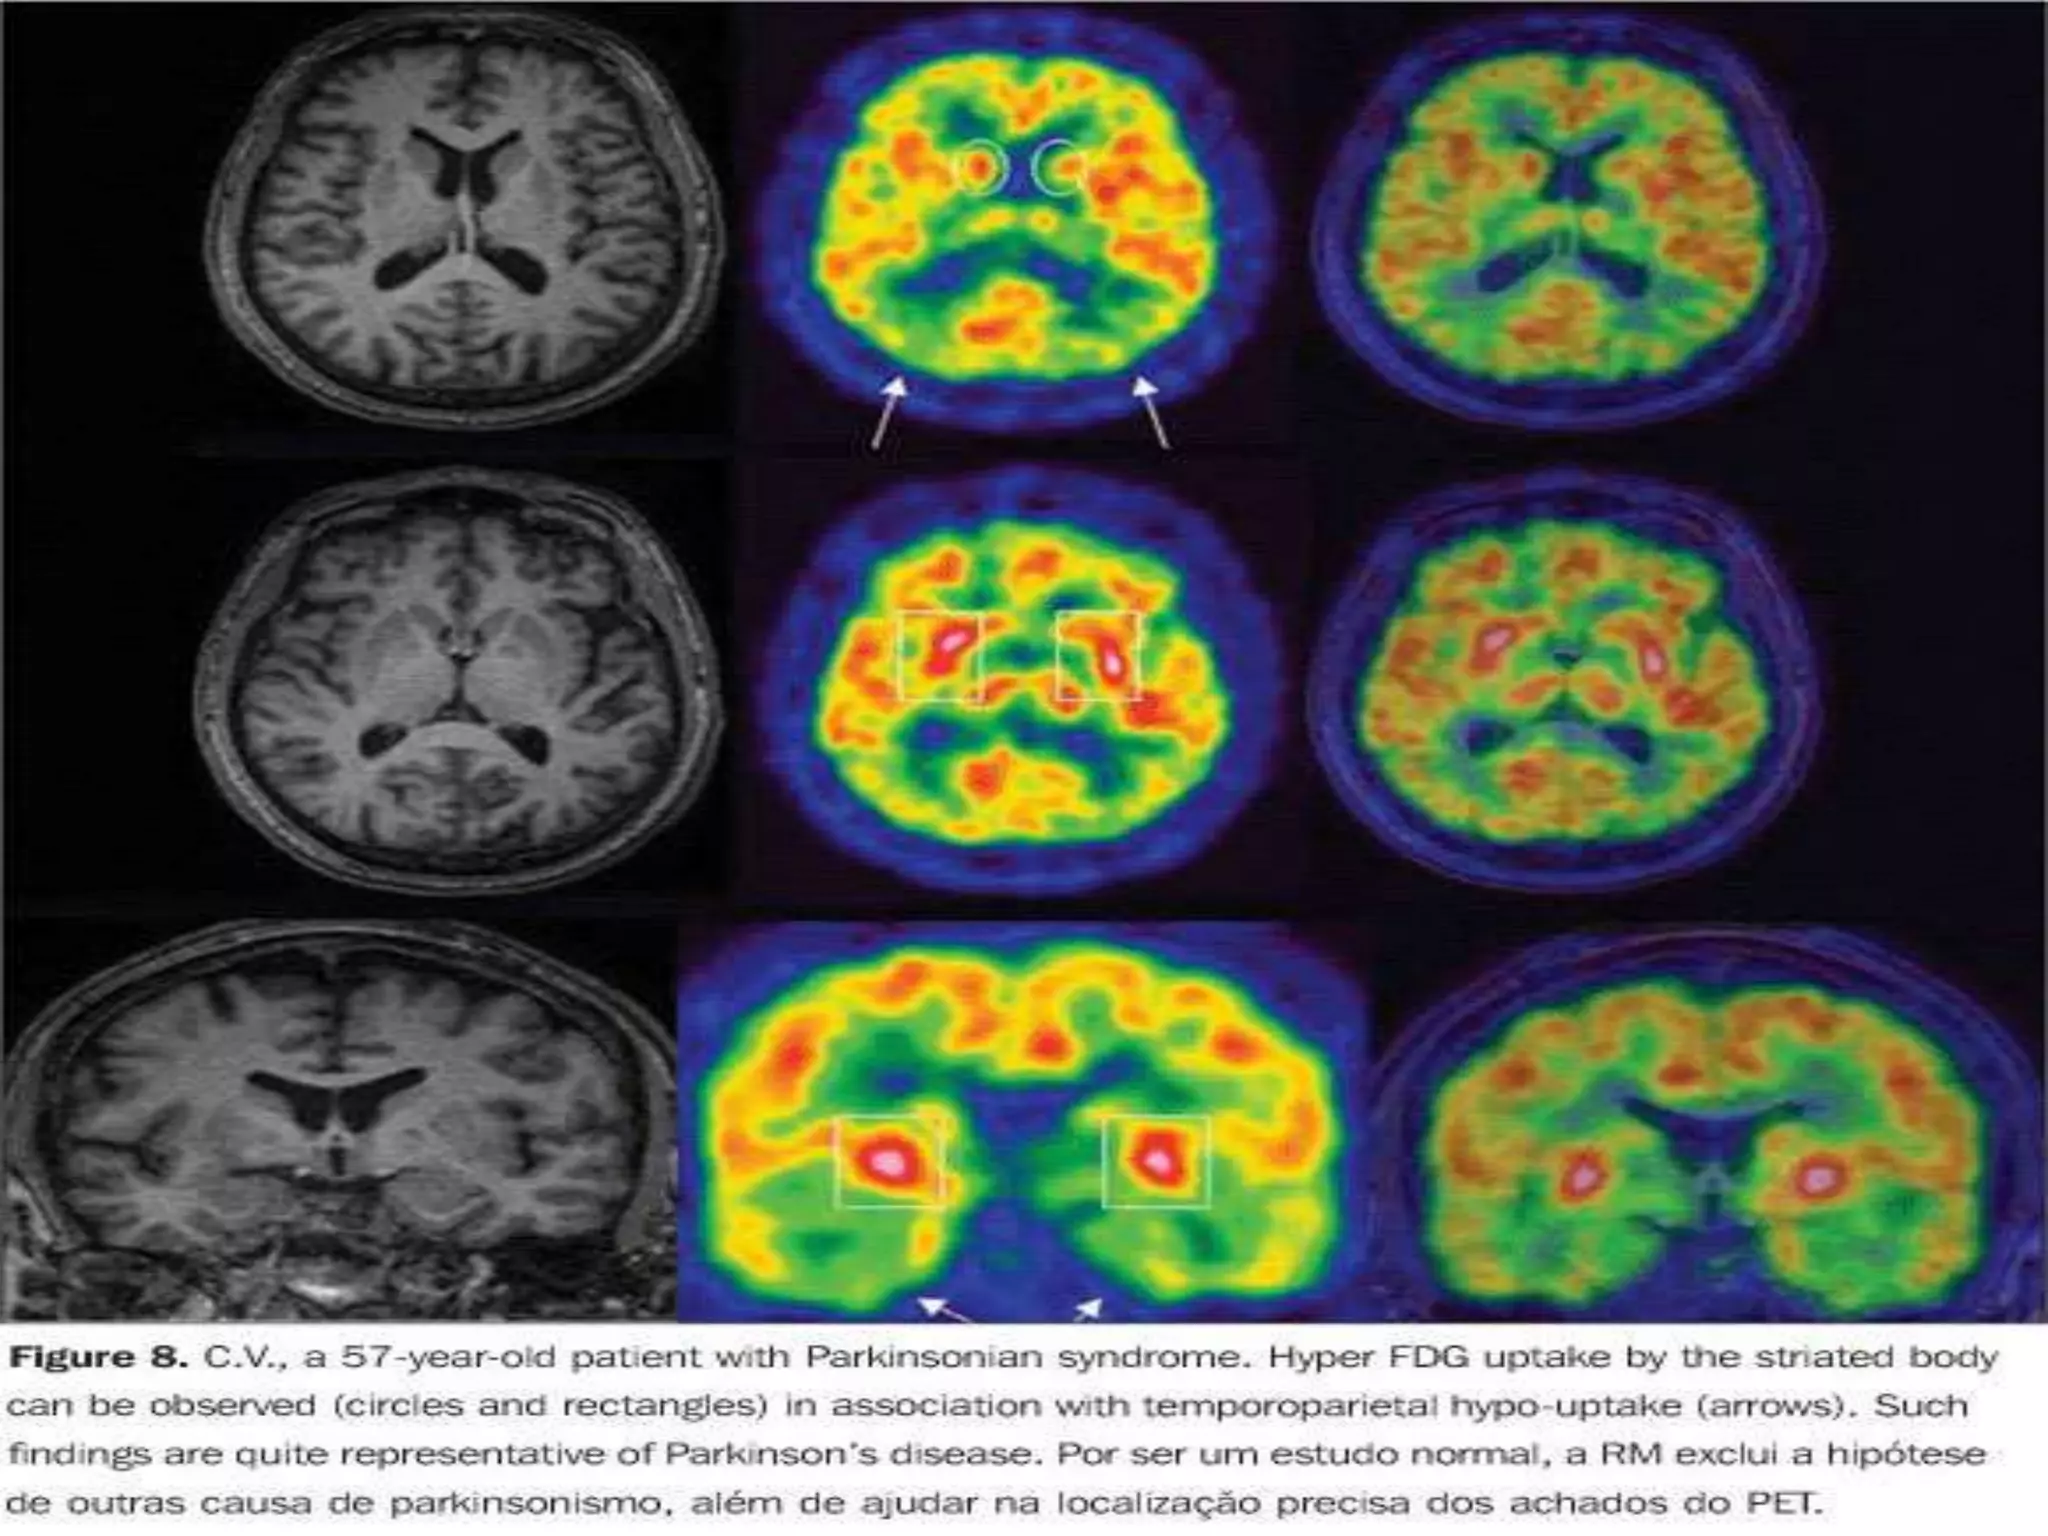

Fluid-attenuated inversion recovery magnetic resonance imaging sequence of the

brain in a patient with West Nile virus encephalitis with associated parkinsonism

and tremor, displaying signal abnormality in the substantia nigra (short arrow),

the mesial temporal lobe (long arrow) and right posterior thalamus (thick arrow).

Fluid-attenuated inversion recoverymagnetic resonance imaging sequence of the brain in a patient with West Nile virus encephalitis with associated parkinsonism and tremor, displaying signal abnormality in the substantia nigra (short arrow), the mesial temporal lobe (long arrow) and right posterior thalamus (thick arrow).